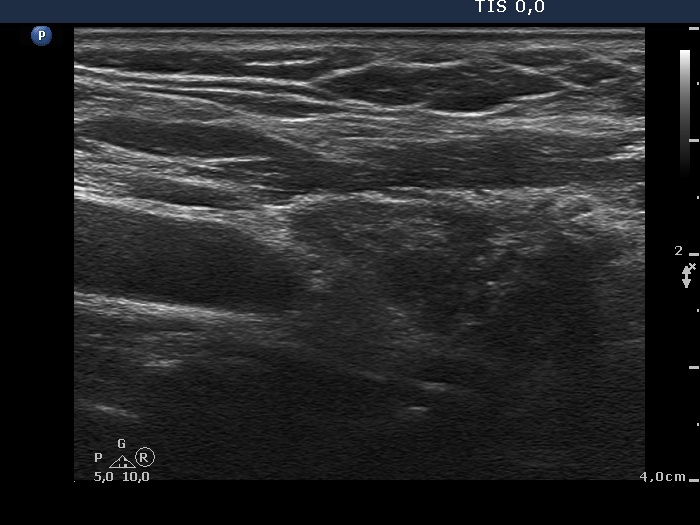

Discrete lesion or nodule in Hashimoto's thyroiditis - case 15 (714) (ultrasonographic picture 3)

Right lobe, longitudinal view. These hypoechogenic areas correspond to more active foci of thyroiditis.